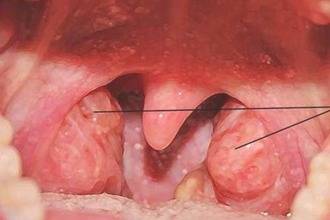

Глотка расположена между третьим и четвертым позвонками шеи и имеет только две стенки: боковую и заднюю. Это уникальное место, где дыхательная и пищеварительная системы пересекаются. Мягкое небо отделяет глотку от ротовой полости с помощью корня языка и мягкого неба. Особая слизистая складка действует как «заслонка», которая изолирует носоглотку во время глотания и разговора.

В глотке на её верхней и боковых поверхностях находятся миндалины, которые представляют собой скопление лимфоидной ткани и называются глоточные и трубные миндалины. Ниже приведена схема разреза глотки, которая поможет более наглядно представить её структуру.